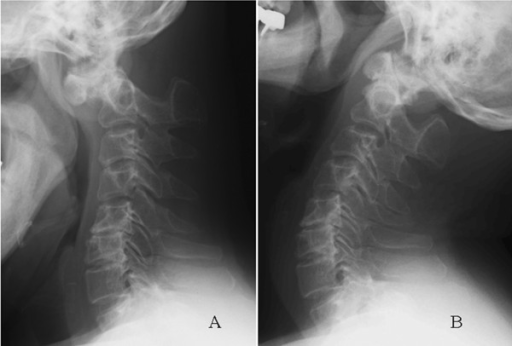

Atlantoaxial instability refers to excessive translation at the joint between the first cervical vertebra (atlas) and the second cervical vertebra (axis) during flexion and extension. Instability at this joint can lead to stenosis of the spinal canal with neurologic complication.

La progresión natural de esta enfermedad puede llevar a la tetraplejia y muerte súbita secundarias a la inestabilidad atlantoaxial y a la compresión medular. Los niños con MPS IVA tienen hipoplasia de odontoides, laxitud articular y depósitos extradurales de GAG anteriores a la médula a nivel de C1 que pueden resultar en subluxación atlantoaxial, estenosis y mielopatía cervical.

In the cervical spine atlantoaxial instability, because of occipitalization of C1 in association with stenosis of the foramen magnum, can be a problem.